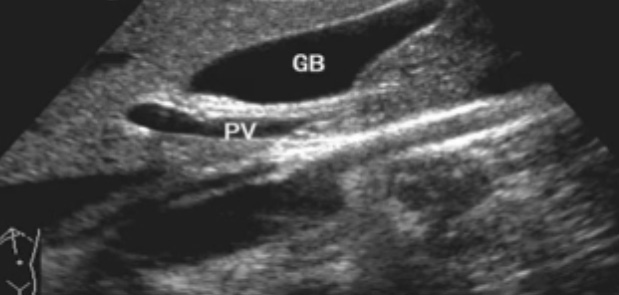

一、正常膽囊超聲圖像有的時候經常發現檢查不到膽囊,其實有幾種可能性,檢查人員的技術不過關沒發現膽囊,就要找上級醫生會診,如果還是沒找到的話就不是技術問題。結石或腫瘤充滿膽囊,使其液腔消失,慢性膽囊炎使得膽囊萎縮或膽囊壁肥厚而囊腔消失患者已進食,膽囊處于膽汁排空的狀態,膽囊先天性過小或缺失;膽囊位置極端異常(可能很低或位于左側)膽囊切除術后(注意詢問病史)。